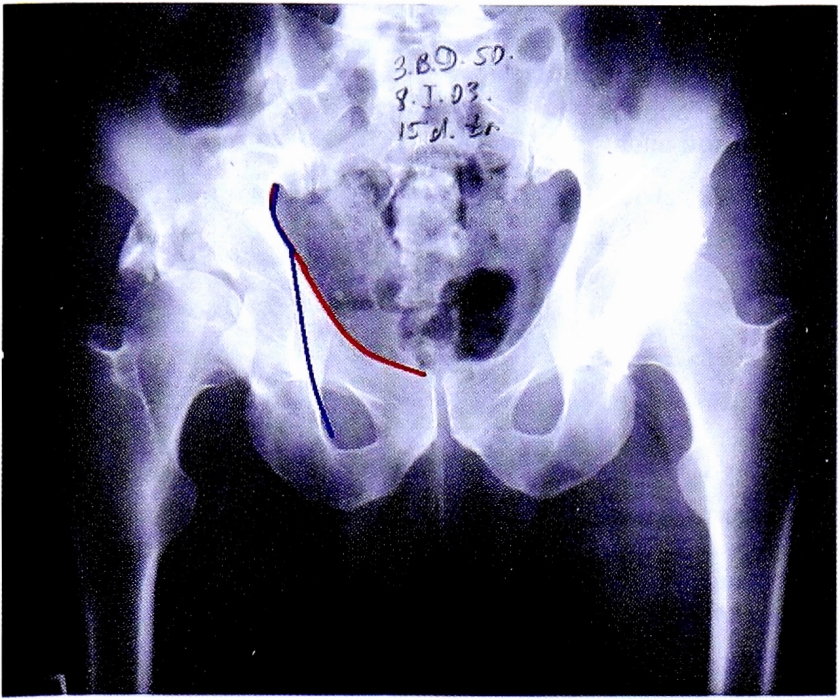

Прямая обзорная рентгенограмма в переднезадней проекции позволяет определить соотношения головки бедра и вертлужной впадины по соответствию стояния головки бедренной кости противоположной стороны (при односторонних переломах), по симметричности линий Шентона. Изменение линии Шентона с большой долей вероятности может свидетельствовать о центральном или краниальном смещении головки бедренной кости, а также о сопутствующем повреждении проксимального отдела бедренной кости. Учитывая индивидуальные особенности тазобедренного сустава сравнение всегда надо проводить с интактным суставом (рис. 8).

Рис. 8. Линия Шентона на обзорной рентгенограмме и на схематическом изображении таза.

Fig. 8. Shenton line on AP pelvic X-ray and on schematic pelvis.